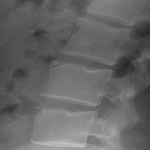

2. Limbus Bone

A limbus bone is an unfused secondary ossification center of the vertebral body (typically the anterosuperior corner), due to herniation of the nucleus pulposus through the ring apophysis prior to skeletal development. This fragment remains ununited to the vertebral body throughout the patient’s life. This can be differentiated from a fracture in that it is well-corticated, triangular, and the fragment of bone will not exactly “fit” into the defect. These fragments may be smaller than the defect of the bone (figure 2) or they may hypertrophy over time and become larger (figure 3). A limbus bone is most often asymptomatic.